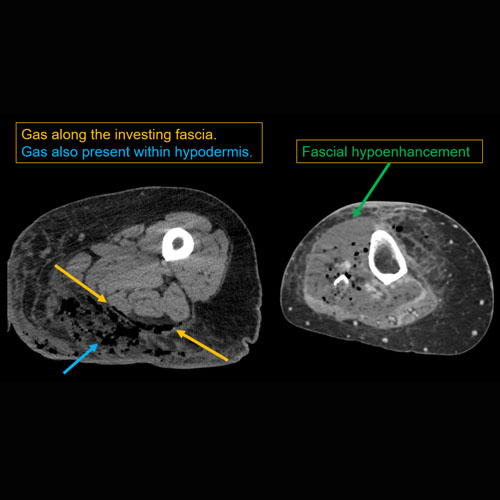

There is hypoenhancement or gas along the fascia.

[Yes/No]